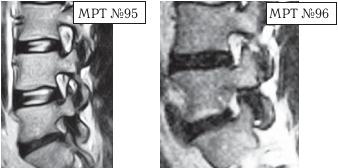

На МРТ № 95 и МРТ № 96 наблюдается практически идентичная картина дегенеративно-дистрофического процесса в поясничном отделе позвоночника у двух разных людей. Исправление физиологического лордоза, значительное снижение высоты межпозвонкового диска в сегменте LV—SI. За счёт сглаживания лордоза суставные поверхности дугоотростчатых суставов, подобно створкам раковины моллюска, раскрываются, суставная капсула растягивается, работа сустава извращается.

В данных случаях в сегментах LV—SI отмечается значительное снижение высоты межпозвонковых дисков, что приводит к образованию подвывиха в дугоотростчатых суставах, который сопровождается смещением верхних суставных отростков нижележащих позвонков кверху и несколько кпереди, стремлением упереться в дужку вышерасположенного позвонка. В нижнем сегменте (МРТ № 96) отчётливо видно, что вследствие подвывиха и смещения суставов образуется не только стеноз межпозвонкового отверстия, но (что важно) происходит и перерастяжение суставной капсулы. В такой ситуации даже сигналы рецепторов дугоотростчатых суставов уже не в состоянии «погасить» возникшую боль.